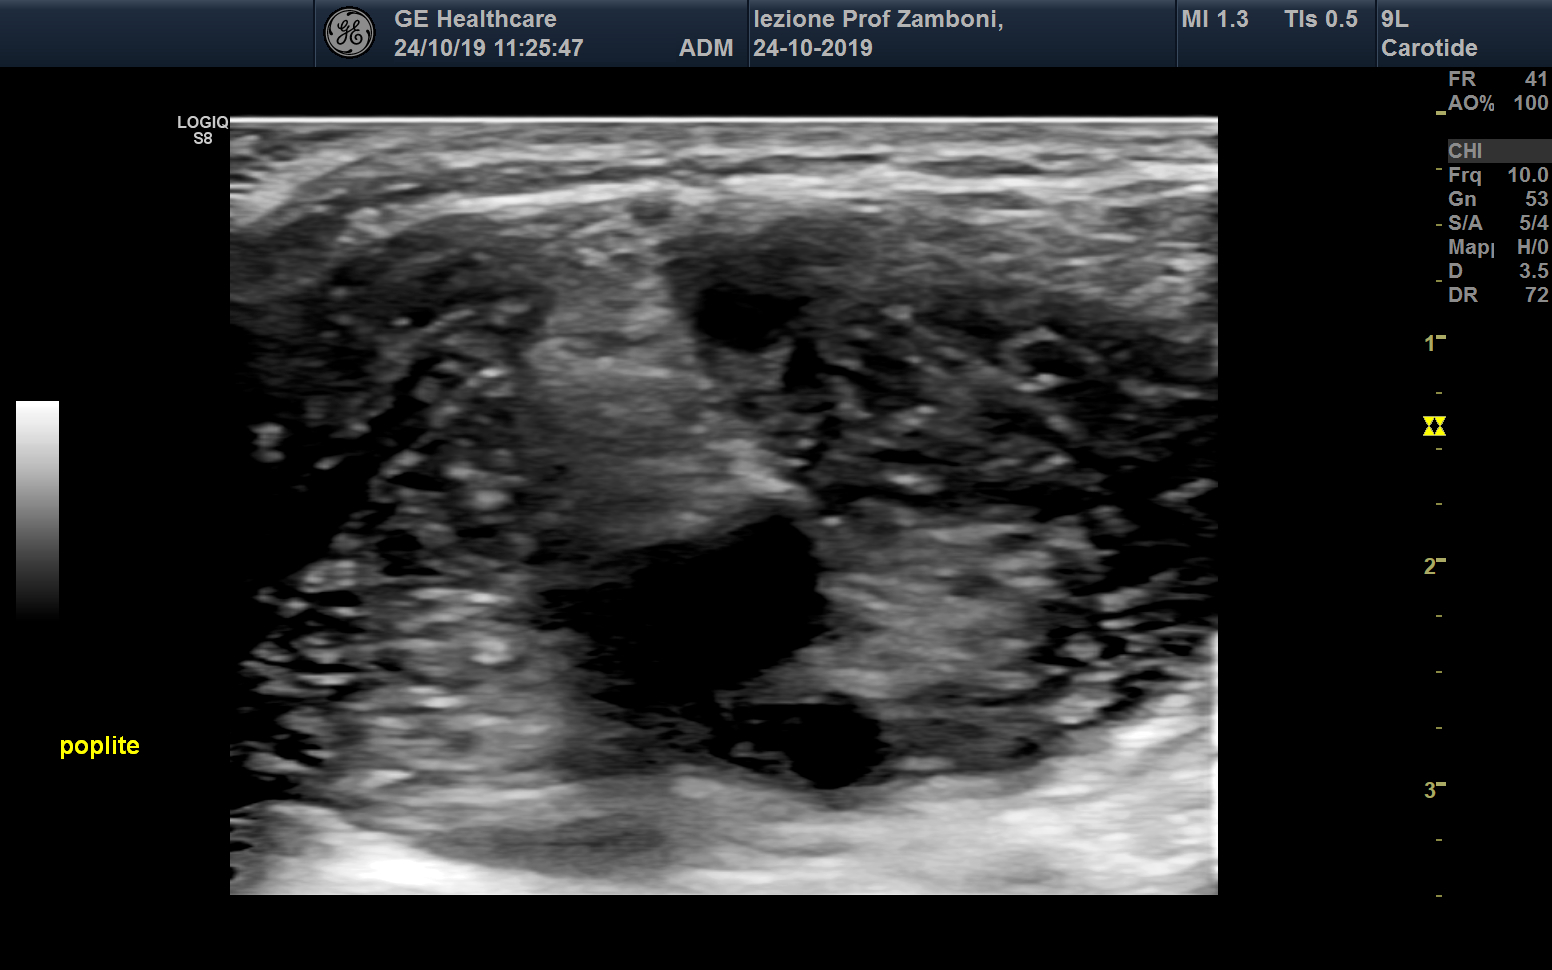

B mode cavo popliteo

JPEG image icon B mode cavo popliteo.jpg — JPEG image, 451 kB (461856 bytes)